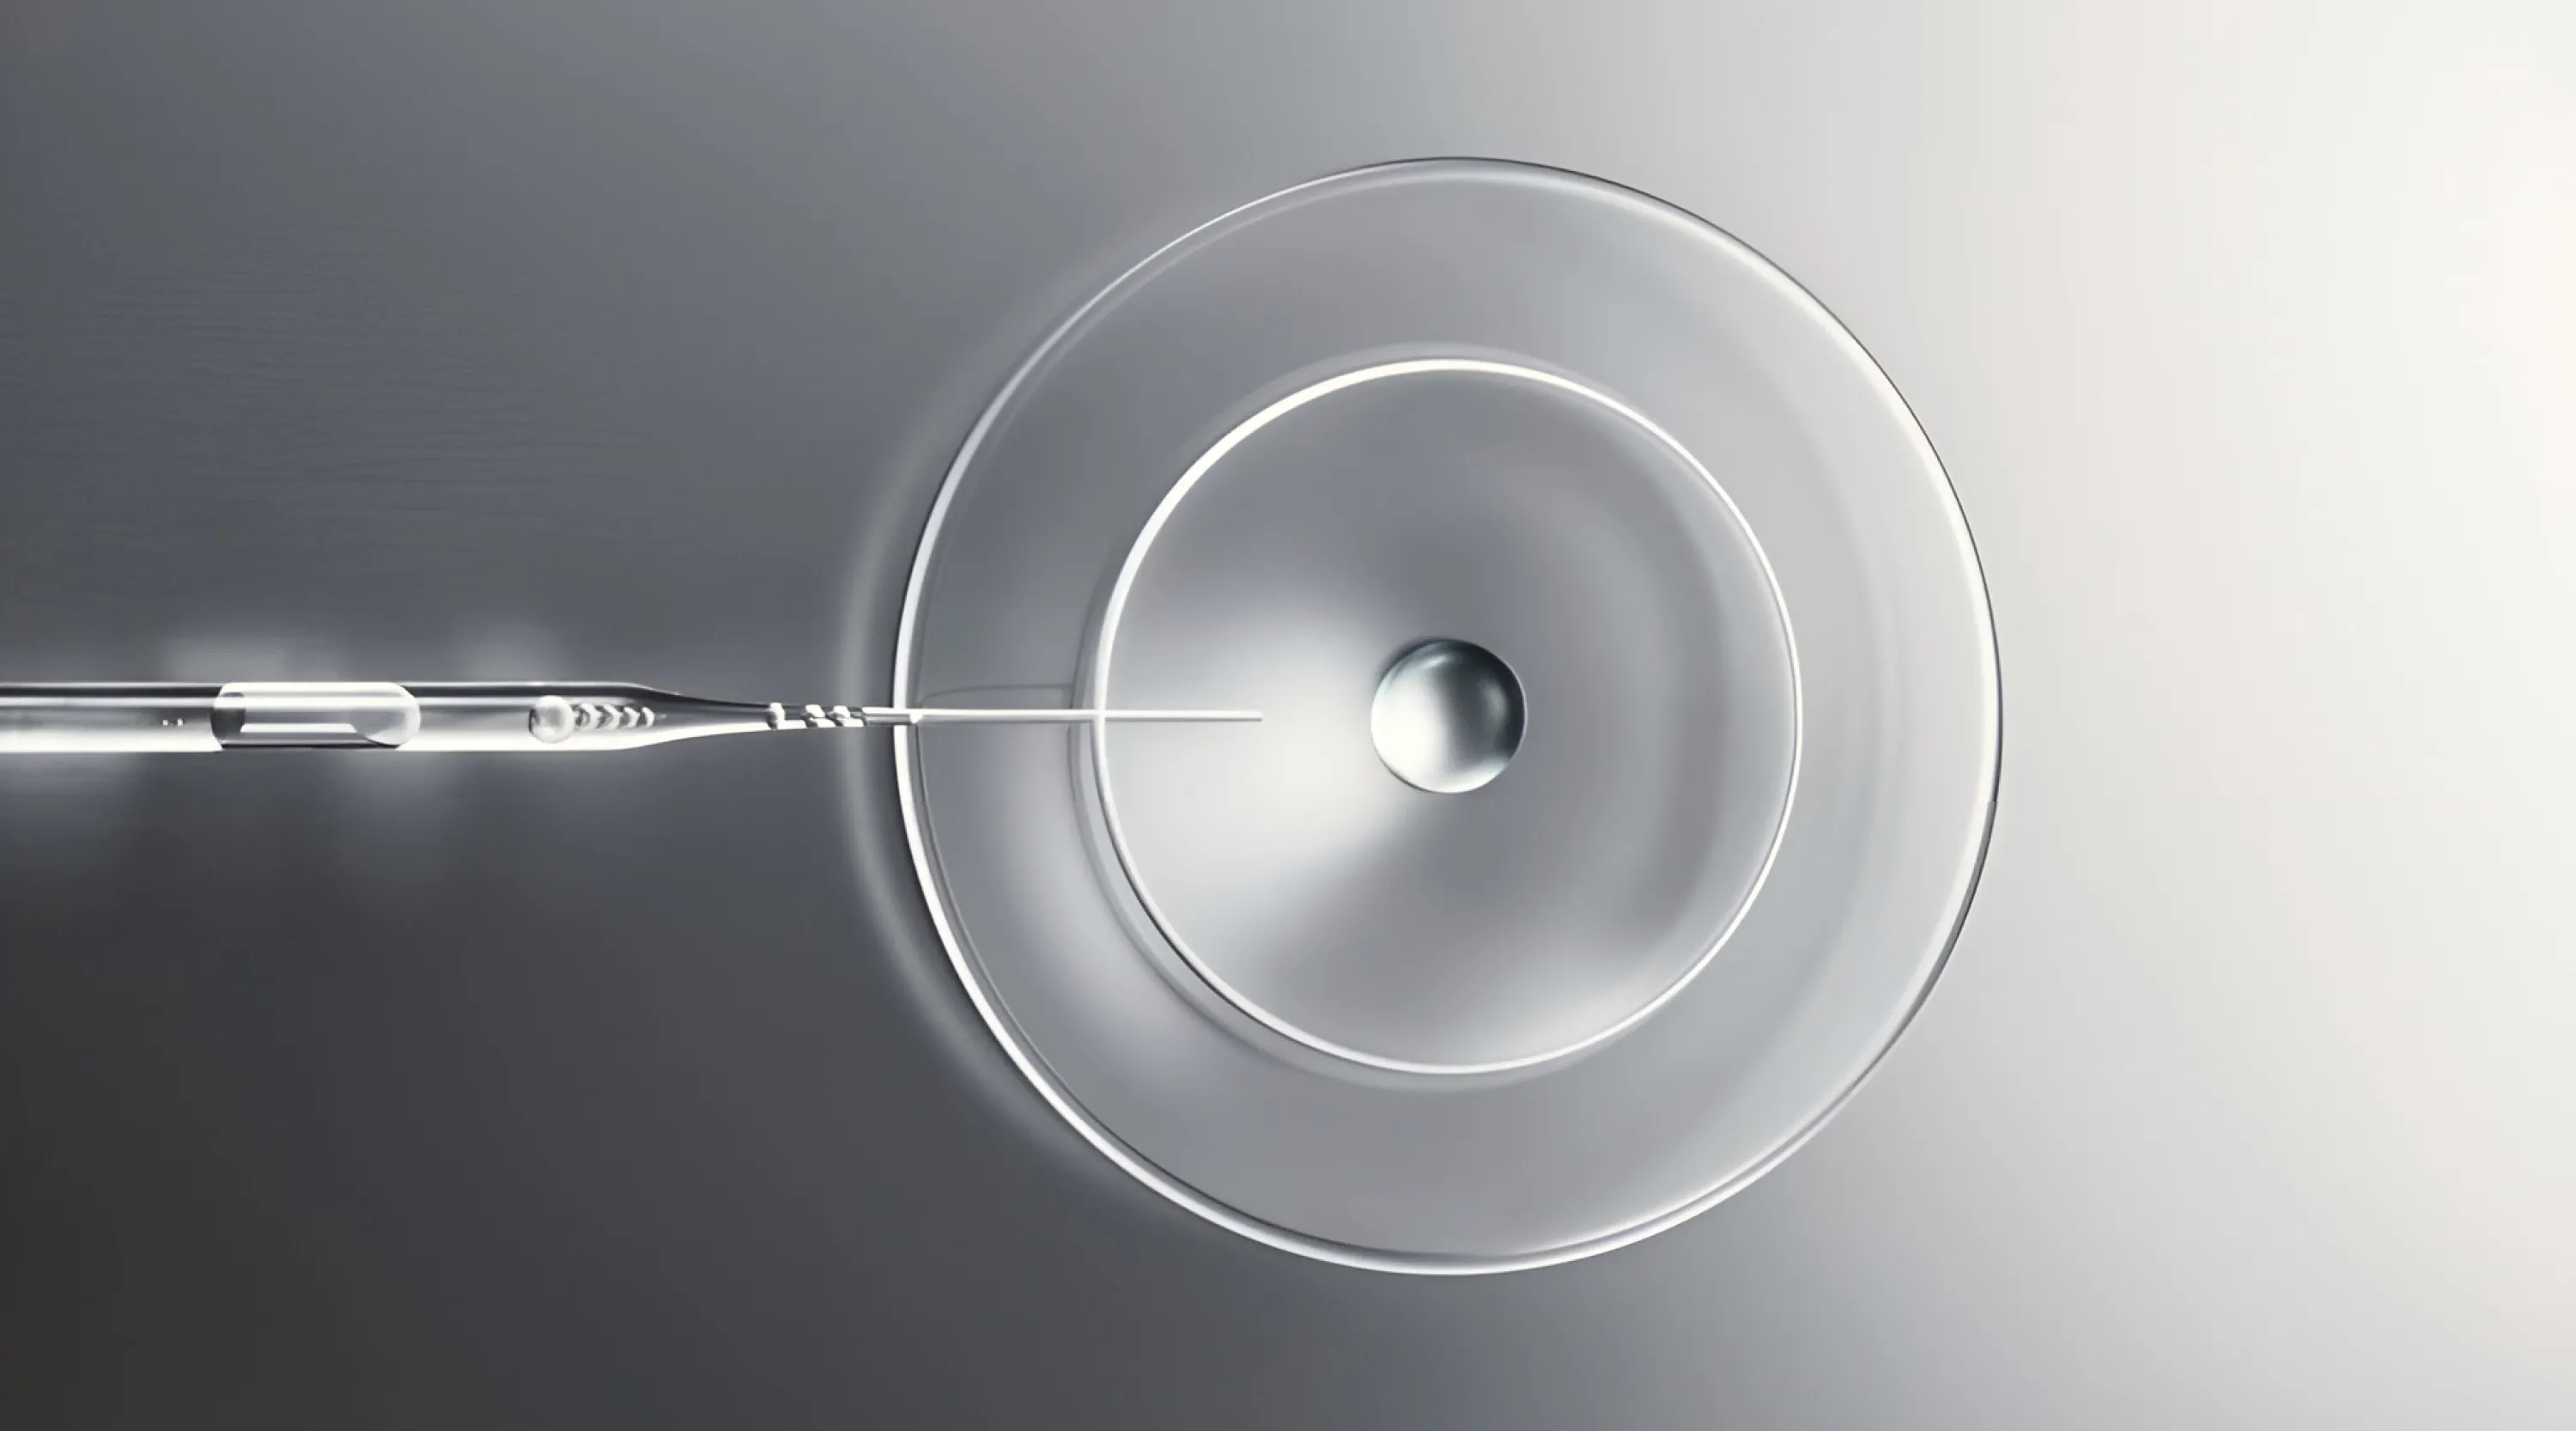

Натуральный инъекционный коллаген, способствующий восстановлению дермы за счет активации коллагеногенеза. Уникальный биоматериал на основе природного коллагена способствует регенерации тканей, стимулирует образование новых коллагеновых волокон, решает широкий спектр эстетических задач. Благодаря инъекциям Коллост кожа становится более упругой и подтянутой, овал лица обретает более четкие контуры, значительно выравнивается рельеф кожи в областях с рубцовыми деформациями, визуальные признаки старения становятся менее заметными.

Ваша кожа утратила былую упругость, стала неприятно бугристой, её обезобразили рубцы или появились стрии, именуемые в народе «растяжками»? Не волнуйтесь: чтобы восстановить кожу, сделать её по-прежнему эластичной и сияющей здоровьем молодости, не обязательно прибегать к оперативному вмешательству. Средства восстановления упругости кожи уже известны — это гель КОЛЛОСТ®.